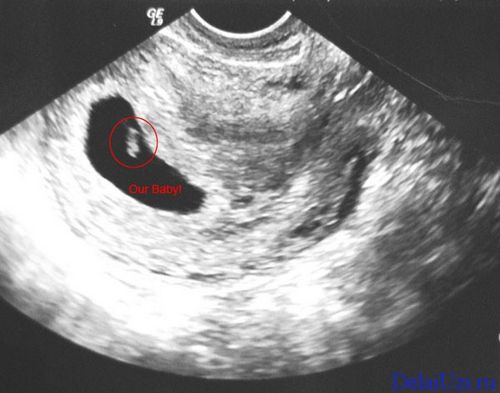

На 6 тижні вагітності по фото УЗД розмір плода встановить абсолютно чітко - це зовсім малесеньке, але вже цілком жива істота. Розмір плода фото УЗД показує дуже добре. Він досягає, всього на всього, 1,5 см. Саме на шостому тижні починають формуватися нервові закінчення в ручках і ніжках, а нервові клітини займають свої місця по всьому організму. Це говорить про те, що малюк скоро почне все відчувати, і буде поступово вчитися рухатися. За допомогою УЗД на цьому тижні вагітності лікар перевірить важливу особливість - як розвивається головний мозок плоду. До цього часу всі три частини «розумового відділу» дитини повинні бути сформовані. Фото УЗД допоможе виключити патології. Розмір плода фото УЗД для досвідченого лікаря може багато про що рассказать.Особенно це важливо, якщо є сумніви в правильному розвитку. З'являються невеликі пухирці, які незабаром стануть чудовими очима. Дивно, але зір - це той важливий орган, який буде формуватися протягом всієї вагітності і завершиться тільки після пологів. Починають формуватися легкі. В організмі все відбувається поступово, для кожного процесу є свій термін. Але завдяки таким знанням, ви можете, нарешті - то усвідомити, що всередині вас перебуває справжнє живе диво - ваш майбутній малюк. І нехай зараз - на шостому тижні, він зовсім не схожий на немовля, він вже є таким.

Розмір плода фото УЗД на даному терміні вагітності показує чітко і ясно. Але крім того УЗД в першому триместрі вкрай важливо для встановлення наявності патологій і загроз для життя як матері так і ребенка.Но все ж варто пам'ятати і про те, що не варто робити фото УЗД без показань лікар, а просто з цікавості побачити майбутню дитину. Справа в тому, що навіть якщо ви хочете побачити свою майбутню дитину цьому тижні вагітності, то вам це навряд чи вдасться.

Монітор покаже лише невелику точку на екрані, а вся отримана інформація від ультразвуку буде корисна виключно лікаря, а не жінці. Тому багато лікарів не радить проводити УЗД на занадто ранньому терміні, без вагомих на те причин.

Фото УЗД покаже, що на цьому тижні протікання вагітності розмір дитини досягає невеликої горошини. Але завдяки тому, що медицина сьогодні пішла далеко, УЗД може встановити розмір плода з точністю до міліметра. Як відбуваються виміри?

Для початку у малюка необхідно знайти куприк і визначити тім'яну зону. На фото УЗД це буде абсолютно невелику відстань, але все ж і його можна виміряти. Відстань між цими зонами називається довгою плода і на шостому тижні вагітності досягає всього пари міліметрів.

Фото УЗД розмір плода визначає точно і це важливо для першого триместру. Саме перше проведене УЗД допоможе лікарю встановити найбільш точний термін пологів. Це важливо в тому випадку, коли у вагітної до пологів не була регулярний або непостійний менструальний цикл або вона просто не пам'ятає необхідних дат. В основному, на шостому тижні УЗД проводиться для того, що б встановити достовірність вагітності - її наявність. До цього терміну матка починає збільшуватися і фото УЗД фіксує ці зміни. Для того, що б більш точно встановити розмір плода і термін вагітності за допомогою УЗД також проводять дослідження плодового мішка. Допоможе у встановленні термінів і серцебиття вашого малюка. Апарат УЗД вловлює скорочення сердечка, виводить їх на екран і динамік. Мама може насолоджуватися, а лікар завдяки цим звукам встановить термін розвитку ембріона, яким повинен бути розмір плода і визначить за допомогою УЗД безпосередньо сам термін вагітності і дату можливих пологів.